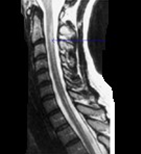

131、单项选择题

患者,女性,23岁,11天前出现发热、头痛和全身酸痛,近两天出现颈背疼痛,四肢无力,查体四肢肌张力低,腱反射消失,病理征(-),C平面以下痛觉减退,尿潴留,行颈髓MRIT2加权像出现如图所示病变。最可能的诊断是()